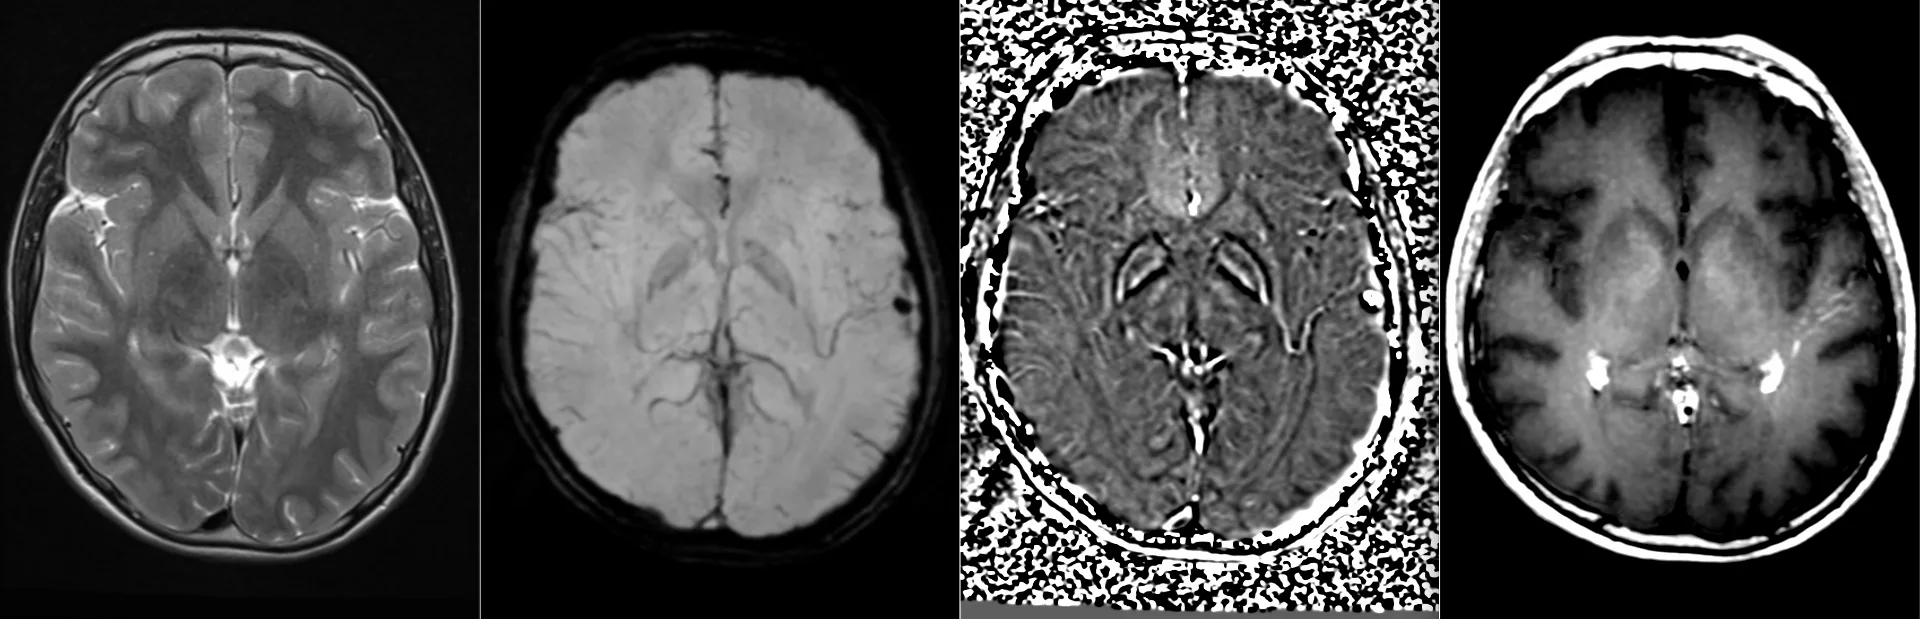

Женщина 32 года. Больной считает себя с 2024 г, когда стала отмечать онемение угла рта. Со слов пациентки ей был предварительно выставлен диагноз - РС, но дополнительных методов обследования и специфического лечения не проводилось. В настоящее время жалоб нет. В исследовании от октября 2024 отмечался очаг в левой затылочной доле с выраженным контрастированием, в настоящее время этот же очаг отмечается с сохраняющимся контрастированием. Формально - есть выполнение критериев диссеминации и в пространстве (юкстакортикальный и перивентрикулярный очаги есть), и во времени (есть усиливающиеся и неусиливающиеся очаги), клиника тоже вполне укладывается. Но! Найти в литературе подобных случаев мне не удалось, видел сам и максимум, что находил в литературе - полгода контрастирования. Получается, мы имеем дело с крайне атипичным рассеянным склерозом, или это не рассеянный склероз. А тогда что? Сосудистая мальформация не вариант - на SWI не видать. Какая-то ганглиоглиома? А другие очаги тогда что? Есть соображения? Кстати, диффузия стойко повышенная, и на б1000 почти не видно (изо). На Т2 не меняется